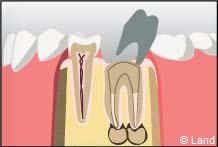

On peut élaborer un inlay avec un ou plusieurs tenons, en fonction du nombre de racines de la dent traitée. Lorsque les axes des canaux radiculaires ne sont pas parallèles, on peut utiliser un ou deux tenons (ou clavettes) distincts de la masse de l’inlay-core.